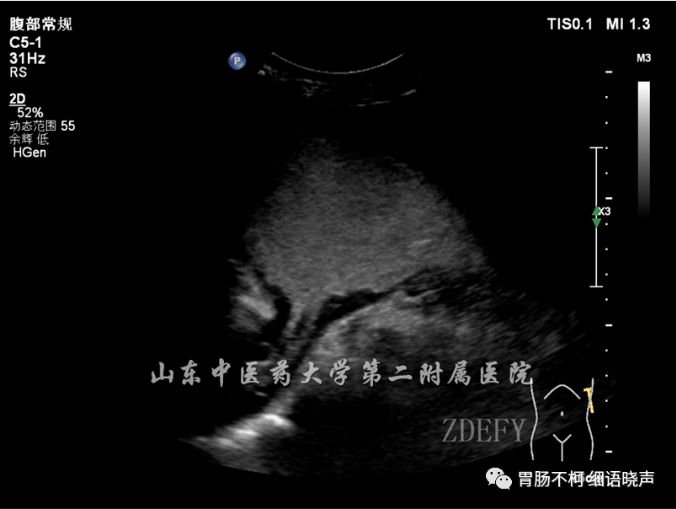

病例四,胃窦壁弥漫性增厚,层次不清晰: